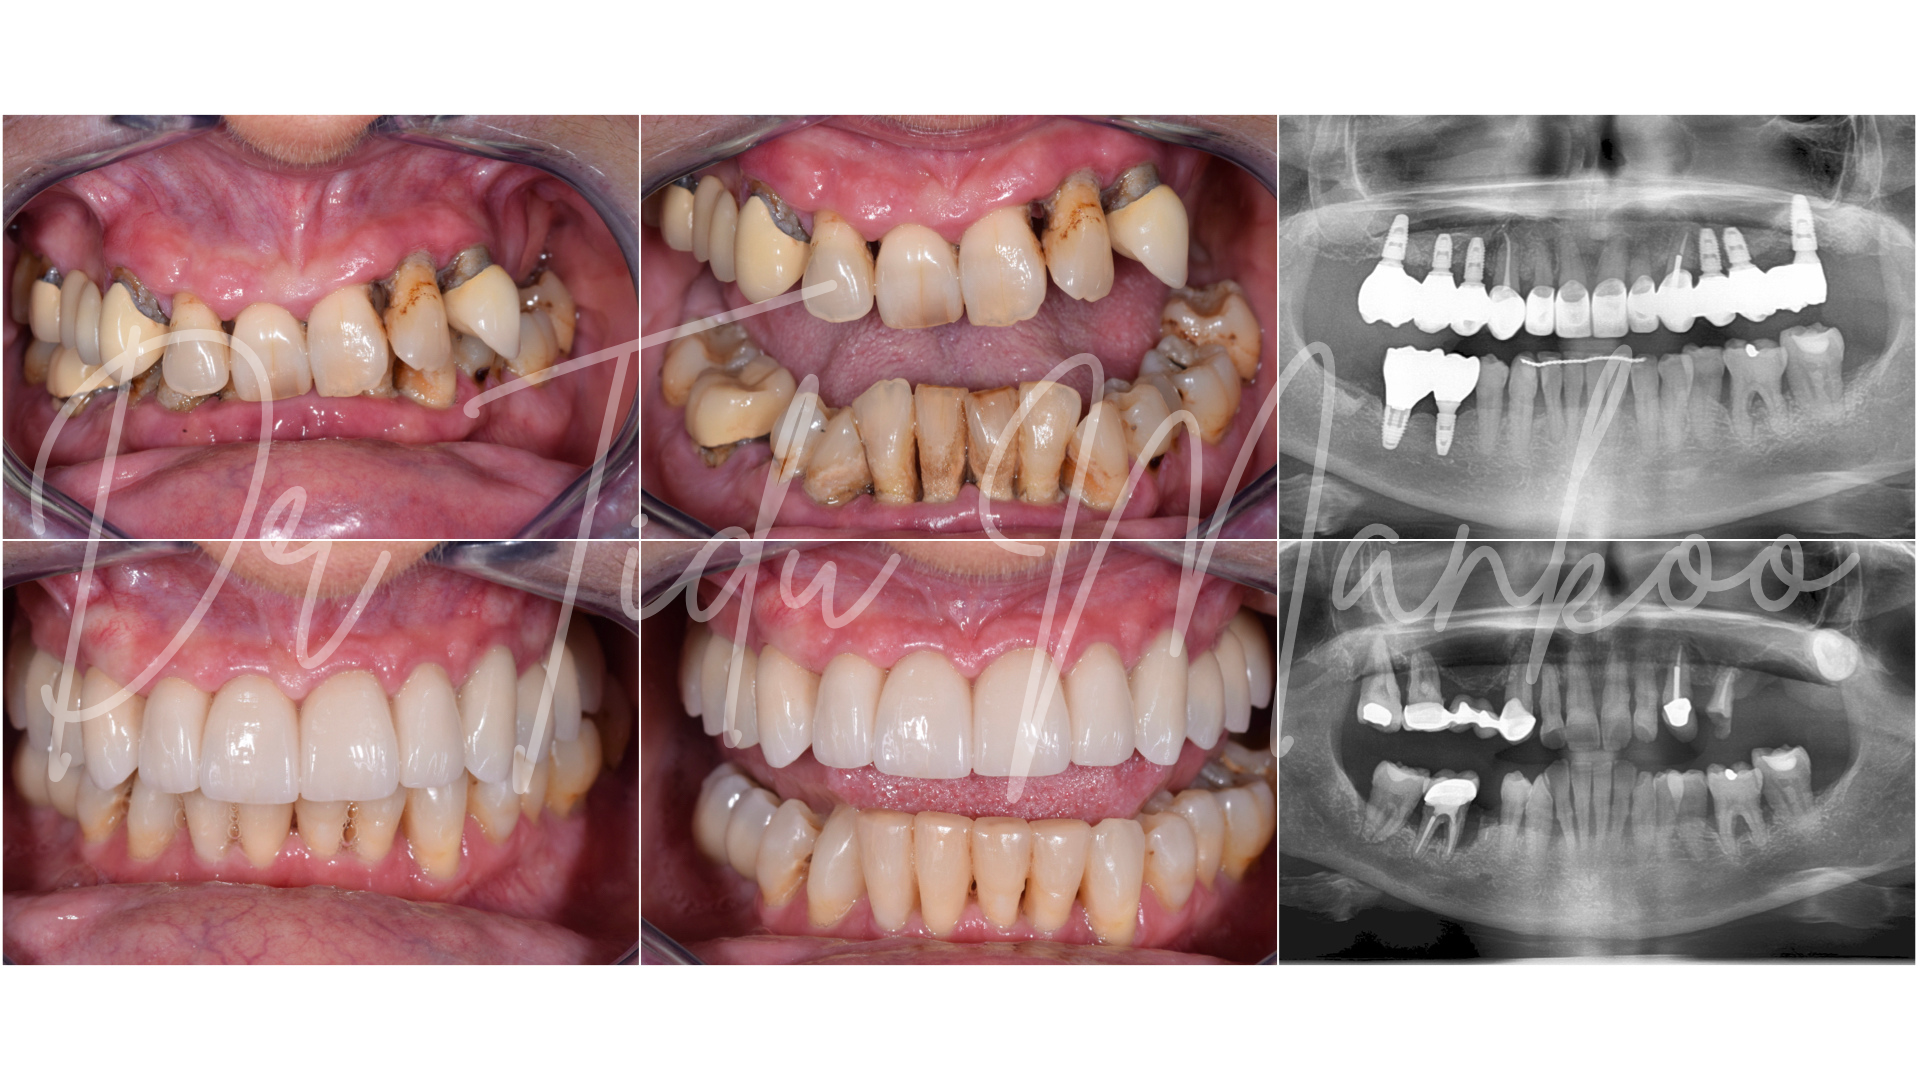

Participants have the fantastic opportunity to learn from a world renowned master clinician of outstanding expertise and experience. This course will outline the contemporary surgical and prosthetic concepts in management of teeth and implants with a view to achieving optimum long-term aesthetics, durability and stability. The emphasis will be on the clinical management and an understanding and application of the biological factors that influence our treatment outcomes. Management of bone, soft tissue and prosthetics contours and materials all play a key part in the aesthetic outcome and long-term stability of soft tissue aesthetics.

Interdisciplinary management of failed implants, severe alveolar defects and periodontally compromised teeth in the aesthetic zone:

• Failed implants and/or grafts and management of complex defects in the aesthetic zone Aesthetic management of periodontally compromised teeth

• Understand the surgical and prosthetic keys to long-term success with implants in the aesthetic zone

• Learn the current concepts in muco-gingival surgery and ‘pink’ aesthetics on teeth and implants to achieve the optimum long term results

• Gain an understanding of the biology of the peri-implant tissues and comprehend the behaviour of the bone & soft tissues in edentulous sites, post extraction sites and around dental implants

• Interdisciplinary management of severe alveolar defects, failed implants and periodontally compromised teeth in the aesthetic zone